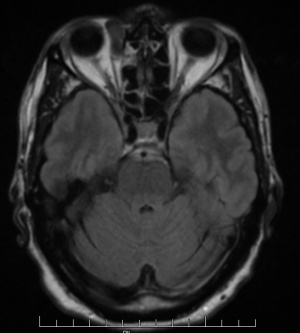

Ultrasonography of solitary fibrous tumors demonstrates low internal reflectivity with sound wave attenuation.[17] CT scan and MRI can be helpful to narrow the differential diagnosis. However, there is variability in the radiographic and MRI appearance of solitary fibrous tumors, so definitive diagnosis can only be made with histopathologic and immunohistopathologic examination. Generally speaking, solitary fibrous tumors will appear as a well-defined soft tissue mass on CT imaging that strongly enhances and may show bony remodeling if the tumor is longstanding. Significant bony changes in patients who have a history of prior tumor excision are suggestive of possible malignant degeneration.[18] Solitary fibrous tumors tend to be hypointense on T1 weighted images and iso/hypo-intense on T2 weighted images. Intralesional pseudocystic cavities are rare, but have been described,[19] and when present, may suggest malignant transformation in recurrent tumors.[20] After administration of contrast, they also tend to show a washout time intensity curve pattern. They have an apparent diffusion coefficient (ADC) value of more than 1.0 x 10-3mm2/s.[18]